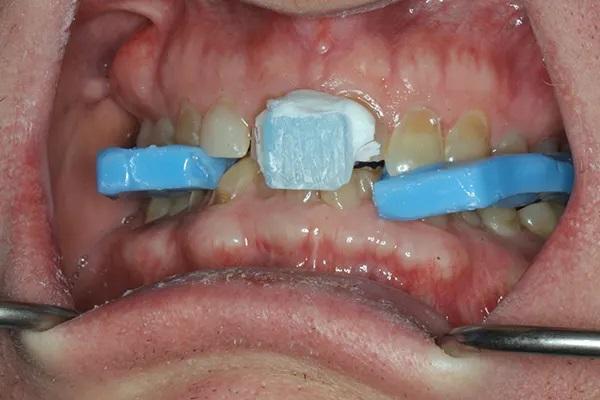

Были получены все необходимые диагностические данные, включая рентгенограммы, фотографии и цифровые сканы. Диагностика приемлемой функции позволила использовать печатную упорную пластину Lucia jig (Kois Center) вместо окклюзионного депрограмматора (Фото 7). Центрическое соотношение было легко обнаружено и зарегистрировано с помощью восковой регистрации прикуса (Фото 8). Фотографии, на которых пациент носит очки для измерения параметров лица (Kois Facial Reference Glasses, Kois Center), были использованы для цифрового монтажа и анализа случая, а также для разработки плана лечения. Резцовый край клыка верхней челюсти располагался у края верхней губы в состоянии покоя. Соответствующее положение центральных резцов верхней и нижней челюсти и задних окклюзионных плоскостей было определено с использованием принципов Центра Койса.

Фото 7: Распечатанная упорная пластина Lucia jig. Обратите внимание на темно-красную точку, обозначающую воспроизводимое положение прикуса (центральное соотношение).

Фото 8: Фиксация прикуса воском выполнена в центральном соотношении.